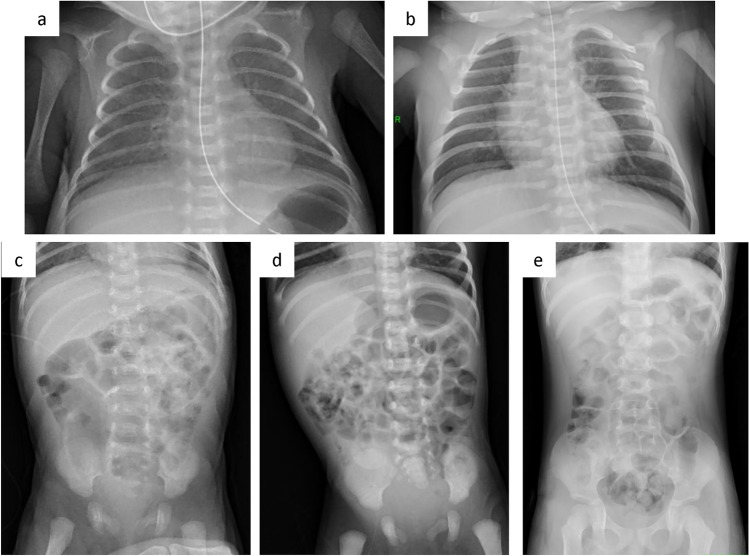

目的:通过视觉分级分析,评估基于人工智能的降噪技术对儿童和新生儿胸腹x线摄影图像退化的补偿影响。材料与方法:选取连续46例儿童和新生儿胸部x线片进行质量评价。图像进行了基于人工智能的降噪处理(智能NR,佳能公司)。所有的图像都是随机的,并由三名委员会认证的放射科医生一致评估从1到4的图像质量。“1”表示没有看到所需的解剖结构或特征,“2”表示质量在1到3之间,“3”表示质量足够,“4”表示高于所需的图像质量。使用Wilcoxon符号秩检验来评估传统降噪图像与基于人工智能的降噪图像之间的显著差异。结果:经过INR(Intelligent NR)降噪处理后的图像质量高于常规处理后的图像质量,两组图像质量差异有统计学意义(p)。结论:基于人工智能的降噪技术可显著提高儿童和新生儿胸腹x线片的图像质量。

Purpose: To evaluate the impact of an AI-based, noise reduction technique for compensation of image degradation on pediatric and neonatal chest and abdomen radiography using a visual grading analysis.

Materials and methods: Forty-six consecutive cases of pediatric and neonatal chest X-rays were identified for the quality evaluation. The images underwent AI-based noise reduction processing (Intelligent NR, Canon Inc.). All the images were randomized, and were evaluated from 1 to 4 for image quality by three board-certified radiologists in consensus. A score of "1" indicated the desired anatomy or features were not seen, "2" indicated quality between one and three, "3" indicated adequate quality, and "4" indicated higher than required image quality. A Wilcoxon signed rank test was used to assess the significant difference between images from conventional noise reduction versus those from the AI-based noise reduction.

Results: The images processed with the INR(Intelligent NR) noise reduction had a higher image quality than the conventionally processed images, with a significant difference between the two groups (p < 0.05).

Conclusion: The AI-based noise reduction technique improved the image quality of pediatric and neonatal chest and abdominal radiography significantly.